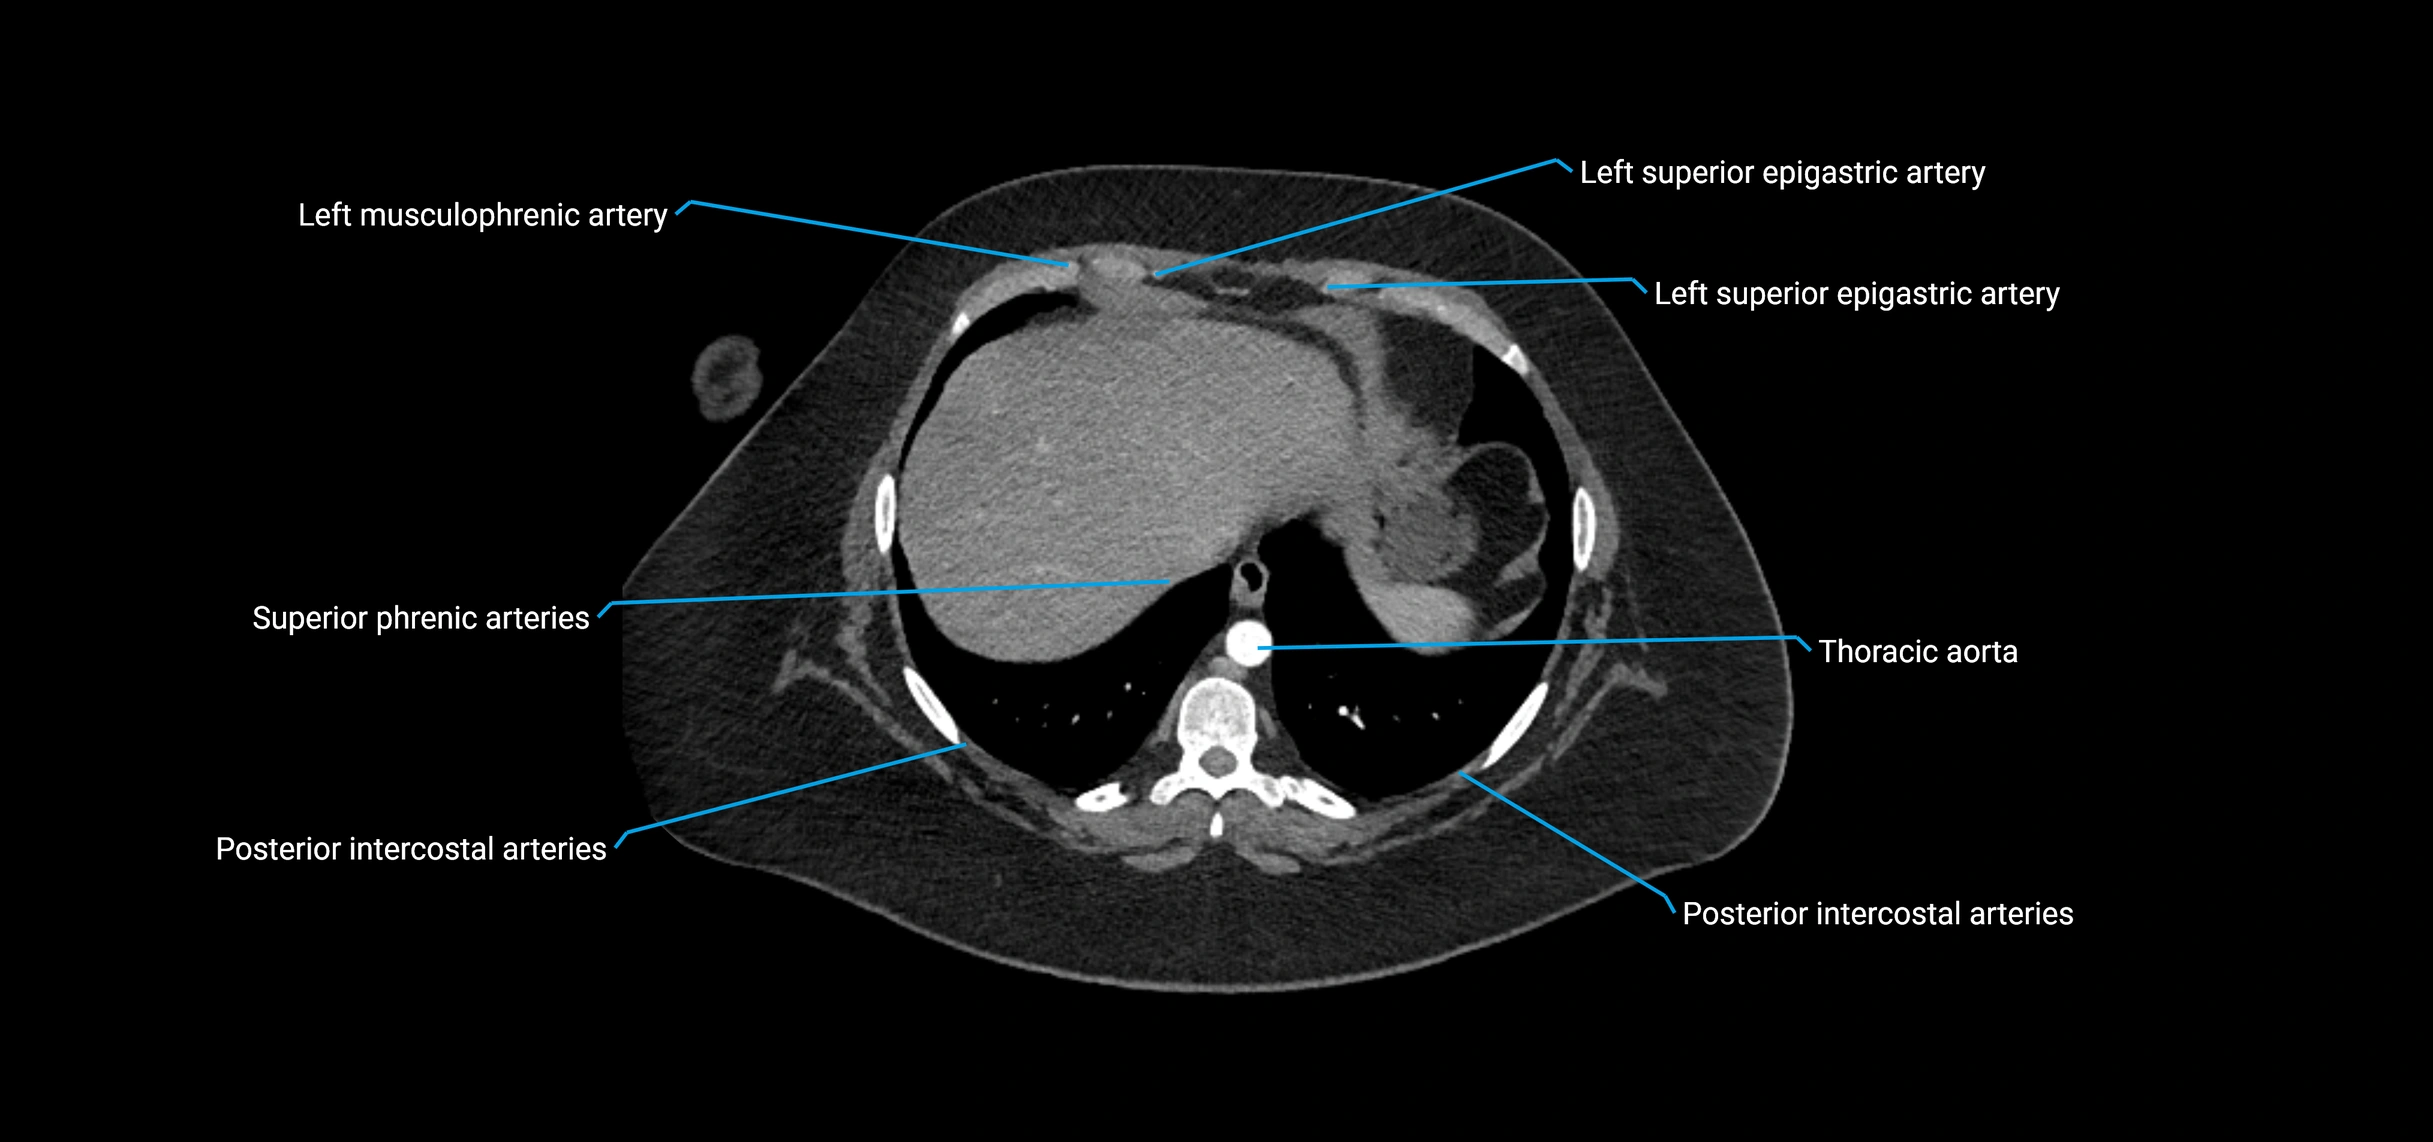

MRI Appearance

T1-weighted images:

• Flowing blood appears as a signal void (black lumen)

• Vessel wall appears as a thin hypointense rim; retroperitoneal fat enhances contrast

T2-weighted images:

• Lumen remains a signal void due to flow

• Adjacent edema, hematoma, or aneurysm wall thrombus may appear hyperintense

T1 Post-Contrast (Gadolinium-enhanced):

• Aortic lumen enhances brightly and homogeneously

• Clearly demonstrates aneurysm, stenosis, dissection, mural thrombus, or aortic wall enhancement in vasculitis